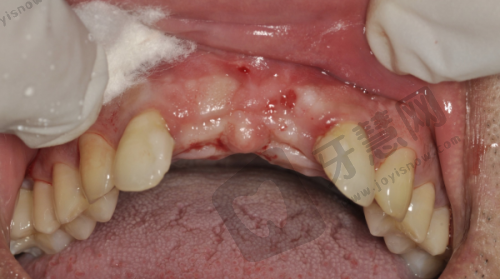

西安高新田园海涛口腔门诊部(田园店)依托海涛口腔集团优势,是一家正规的口腔诊疗机构。诊疗项目丰富,涵盖牙齿修复、牙周治疗、儿童牙科、补牙、牙齿美白、牙齿矫正及种植牙等。特色技术显著,如“1天得”种植技术,将传统治疗时间大幅缩短,真正实现“当天种牙、当天戴冠、当天吃饭”。诊疗环境舒适宜人,严格执行消毒标准,保护患者安心。医院配备CBCT机、全景机、超声洁治器等精良设备,为精细治疗提供有力支持。医生团队经验多,能为患者提供个性化治疗方案。在患者中口碑良好,深受信赖。

1. 种植牙技术:拥有“1天得”种植技术,将传统3 - 8个月的治疗时间缩短至1天,实现当天种牙、当天戴冠、当天吃饭,大大节省患者时间。